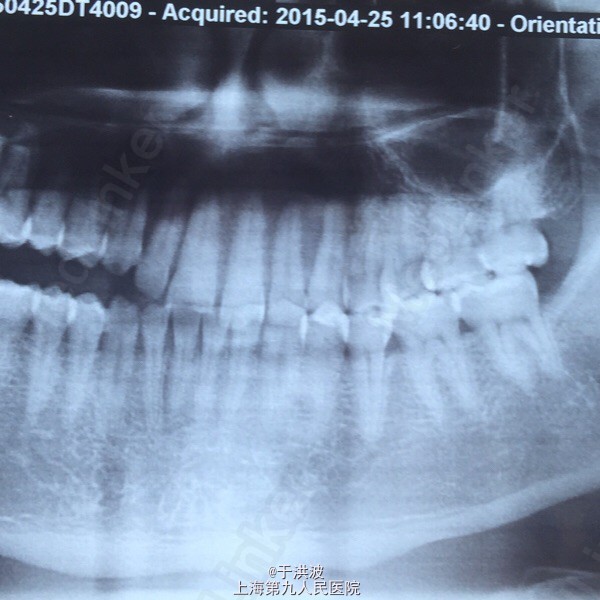

面部基本对称,右侧面部无明显膨胧,无压痛。口内右侧上颌前庭沟黏膜无异常,右侧上颌牙列松动,牙列上移,与下颌牙无咬合接触。CT示右侧上颌骨弥散性吸收。血常规未见异常

右侧上颌骨骨巨细胞瘤?坏死性肉芽肿? 局麻下行切取活检术